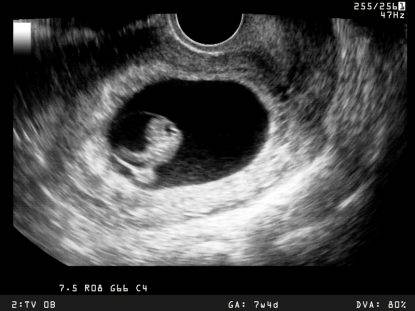

Care unimamme, sapevate che un cuore umano batte in media per 3 miliardi di volte durante la vita? La domanda che ne deriva è: quando inizia a battere il cuore?

Fino ad oggi i ricercatori sapevano che il cuore di un bambino inizia a battere intorno al 21esimo giorno di gravidanza. Ora una nuova ricerca ha dimostrato che non è vero.

Il primo battito avviene a 16 giorni dal concepimento

Infatti fino ad oggi risultava che il cuore dei topi iniziasse a battere 8 giorni dopo il concepimento, che corrispondono a 21 giorni della gravidanza umana. Il nuovo studio invece ha scoperto che il cuore compie il primo battito a 7 giorni, e che corrispondono a 16 nell’uomo.

Nello studio, pubblicato sulla rivista scientifica eLife, i ricercatori hanno scoperto che il muscolo inizia a contrarsi a uno stadio iniziale dello sviluppo del cuore. Nei topi questo avviene a 7,5 giorni dal concepimento, corrispondenti come detto a 16 giorni dell’embrione umano.